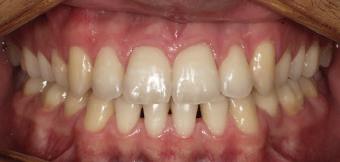

20 Dental Tribune Bulgarian Edition / октомври 2022 г. П ациентите със завършен растеж и скелетни проблеми обикновено представляват предизвикателство за ортодонт ската практика. Необходимостта от изваждане на зъби в комбинация с особеностите на възрастовата ортодонтия изисква особено внима ние. Фокусът върху критично важното значение на позицията на долните резци във връзка с дългосроч ната стабилност и постигането на оптимални оклузални взаимоотношения при затварянето на екстракционните пространства лесно може да излезе извън контрол. Когато към тези чисто кли нични проблеми се добави и стресът от натоваре ната практика, предизвикателството става още по-голямо. Всички тези фактори налагат използ ването на доказан подход с ясни и последовател ни стъпки, в което се разкрива силата на дисциплината „Алекзандър“ – предвидим протокол през целия процес на елиминиране на ротациите, ниве лиране на дъгите, затваряне на екстракционните пространства и финализиране на случая. Именно такъв е и случаят, който презентираме –екстракционен, скелетен клас 3 при възрастен па циент, лекуван по системата „Алекзандър“. ПРЕДВИДИМИ РЕЗУЛТАТИ ПРИ ПАЦИЕНТИ СЪС ЗАВЪРШЕН РАСТЕЖ И СКЕЛЕТЕН КЛАС 3, ИЗПОЛЗВАЙКИ ЕКСТРАКЦИОННО ЛЕЧЕНИЕ ПО ДИСЦИПЛИНАТА „АЛЕКЗАНДЪР“ Д-р Радой Димитров, България Преди започване на лечение клиничен случай | ортодонтия Фиг. 1а–1e Преди започване на лечение. Пациентът пристига в практиката с основното оплакване от невъзмож ност за нормално дъвчене. Снета е цялата необходима диагностична ин формация. Фиг. 1f–1h Снимки в профил и анфас. Фиг. 1i–1k Панорамна снимка, телерентгенография и анализ на телерент генография. Фиг. 1а Фиг. 1d Фиг. 1f Фиг. 1g Фиг. 1h Фиг. 1e Фиг. 1b Фиг. 1c Фиг. 1i Фиг. 1j Фиг. 1k

closed.

21Dental Tribune Bulgarian Edition / октомври 2022 г. ДИАГНОСТИЧНИ РЕЗУЛТАТИ: 1. Възраст на пациента: 21 години 2. Скелетен клас III (ANB 0) 3. Зъбен клас 3 4. Ръбцова захапка във фронта, кръстосана в дисталните участъци 5. Тясна горна челюст 6. Overjet – 0 мм, Overbite – 0 мм 7. Несъответствие на горната с долната средна линия 8. Единични контакти в ЦО 9. Хиподивергентен тип на растеж SN/MP – 33.5 10. Неравен гингивален контур 11. Неравна линия на усмивката 12. Тенденция за рецесии в долен фронт ПРЕПОРЪЧИТЕЛНО ЛЕЧЕНИЕ: Пълно ортодонтско лечение с метални брекети „Алекзандър“ Корекция на клас 3 захапката в областта на кучешките зъби с екстракция на първите пре молари в долна челюст Корекция на кръстосаната захапка в дистални участъци Коригиране на ръбцовата захапка във фронта Подобряване на ОJ и OB на пациента Стрипинг в долен фронт Подреждане на зъбите в горната и долната челюст Професионално хигиенизиране и профилактични дентални прегледи са препоръчителни на всеки 6 месеца. 1-ви месец След 1 месец са залепени брекети в горната челюст – поставена е еластична дъга. 016 NiTi. В долната челюст са елиминирани ротациите, поставена е стоманена дъга. 016SS, закалена с ток, и еластична верижка за затваряне на пространствата. 3-ти месец В долната челюст е поставена трета дъга – 17 x 25 NiTi с къси лигатури и верижка

В горната челюст се затварят пространствата с дъга .016SS и верижка. 5-и месец На 5-ия месец след залепяне на брекетите в долната челюст е поставена стоманена дъга 16 x 22 SS с четвъртито сечение, омега луп и тай бек. В горната челюст е поставена дъга 17 x 25 NiTi. Поради липсата на стабилни оклузални контакти са поставени лингвални верижки в областта на моларите, за да се предотврати нежелана ротация на 7-ите зъби. 6-и месец На 6-ия месец от началото на лечението са екстрахирани долните първи премолари, поставена е дъга 16 x 22 SS със затваряща чупка teardrop. Чупката се активира всеки месец по 1 мм с чинч-бек. клиничен случай | ортодонтия СТЪПКИ НА ЛЕЧЕНИЕТО Начало на лечението Лечението започва с поставяне на апарат за бърза експанзия в горната челюст. През първия месец от лечението са направени 24 оборота на апарата за експанзия. Залепени са брекети в долната челюст, поставена е дъга 17x25 CuNiTi, като са предпи сани клас 3 ластици (1/4”,4 1/2 oz) по време на сън, за да се осигури контрол върху торка на долните резци. Фиг. 2а Фиг. 3a Фиг. 4a Фиг. 3b Фиг. 4b Фиг. 3c Фиг. 4c Фиг. 3d Фиг. 4d Фиг. 3e Фиг. 4e Фиг. 5a Фиг. 5b Фиг. 5c Фиг. 5d Фиг. 5e Фиг. 6a Фиг. 6b Фиг. 6c Фиг. 6d Фиг. 6e Фиг. 7a Фиг. 7b Фиг. 7c Фиг. 7d Фиг. 7e Фиг. 2b Фиг. 2c Фиг. 2d

Dental Tribune Bulgarian Edition / октомври 2022 г.22 клиничен случай | ортодонтия 14-и месец В горната и долната челюст са поставени последни стоманени дъга с омега луп и тай бек – 17 x 25 SS с четвъртито сечение. Назначени е ластик за средната линия в комбинация с клас 3 ластик (1/4”, 6 1/2 oz). Контролни рентгенографии 13-и месец Екстракционните пространства са затворени. Направена е контролна панорамна снимка за оценка позицията на корените. Взето е решение за презалепване на брекетите на 12, 22 и пръстените на 36 и 46. 21-ви месец Средната линия в горната и долната челюст съвпадат. Ластиците са спрени. Свалени са пръстените и брекетите в горната и долната челюст, зигзаг ластици не са използвани поради благоприятните оклузални взаимоотношения. Фиг. 11j Ортопантомография в края на лечението. Фиг. 11k Телерентгенография след края на лечението. Фиг. 11l Анализ на телерентгенографията след лечението. Фиг. 11m Последователност на дъгите в горната и долната челюст Фиг. 11n Суперимпозиция на PreOp и PostOp ортопантомографии. 10-и месец Затварянето на пространствата е предвидимо и контролирано, без да се отварят пространства в зъбната дъга. Фиг. 8a Фиг. 8b Фиг. 8c Фиг. 8d Фиг. 8e Фиг. 10a Фиг. 10b Фиг. 10c Фиг. 10d Фиг. 10e Фиг. 9a Фиг. 9b Фиг. 9c Фиг. 9d Фиг. 9e Фиг. 9f Фиг. 11a Фиг. 11f Фиг. 11j Фиг. 11l Фиг. 11m Фиг. 11n Фиг. 11k Фиг. 11g Фиг. 11h Фиг. 11i Фиг. 11b Фиг. 11c Фиг. 11d Фиг. 11e

Dental Tribune Bulgarian Edition / октомври 2022 г. 23клиничен случай | ортодонтия реклама Лечението е продължило 21 месеца. Проведено е домашно избелване с индивидуални шини. За автора: Д-р Радой Димитров завършва с отличие Факултета по дентална медицина към МУ–София през 2015 г. В продължение на 5 години работи в няколко водещи практики в София, като през 2019 г. заедно със своята съпру га д-р Траяна Димитрова основават собствена практика в гр. Гоце Делчев –Dimitrovi Dental Care. Посещава редица курсове за повишаване на квалификаци ята, но най-сериозен тласък в развитието на ортодонтската си практика получава след завършването на комплексната ортодонтска програма, воде на от д-р Иван Горялов, базирана на дисциплината „Алекзандър“ – система с повече от 50 години опит в целия свят. Д-р Димитров е член на Българския изследователски клуб „Алекзандър“. Взе ма участие като гост-лектор в симпозиума с международно участие The Power of the Alexander Discipline, който се проведе на 14–15.05.2022 г. С д-р Ди митров можете да свържете на тел. +359885 252 025. Заключение Представеният случай е ярък пример за възможностите и красо тата на дисциплината „Алекзандър“ – приложен е утвърден под ход с ясни правила и са постигнати очакваните цели. Резулта тът ще бъде дългосрочно стабилен, тъй като са спазени всички правила, които се отнасят към максимално комфортната пози ция на зъбите в края на лечението. Постигнати са красива усмив ка и стабилна оклузия. ПОСТИГНАТИ РЕЗУЛТАТИ ОТ ЛЕЧЕНИЕТО 1. Коригирана ръбцова захапка 2. Коригирана клас 3 захапка в областта на ку чешките зъби 3. Коригирана кръстосана захапка в дисталните участъци 4. Коригиран овърджет и овърбайт 5. Разширена е горната зъбна дъга 6. Подредени зъби в горната и долната челюст 7. Постигната е стабилна захапка с множество контакти в ЦО 8. Драматично е подобрена дъвкателната функ ция 9. Подобрена е линията на усмивката ДРУГИ ПРОВЕДЕНИ ДЕНТАЛНИ ПРОЦЕДУРИ 1. Домашно избелване на зъбите 2. Екстракция на мъдреците Фиг. 12a Фиг. 12b Фиг. 12c Фиг. 12eФиг. 12d Фиг. 12f Фиг. 12g Информация за дати, цени и отстъпки www.bracescourses.com 0889 22 55 01 Практически курсове лектор д-р Иван Горялов Дисциплината „Алекзандър“ ПЪТЯТ КЪМ СУПЕРУСМИВКИТЕ 100% връщане на цялата сума, ако не сте удовлетворени след преминаване на Ниво 1 Директно и индиректно залепяне на брекети Анализ, диагноза и план на лечение Лечение на клас 2 дълбока захапка Екстракционно лечение Лечение на клас 3 отворена захапка НИВО 5НИВО 1 НИВО 2 НИВО 3 НИВО 4